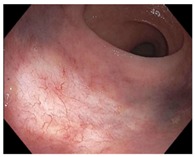

| Endoscopy | Flat white scar Telangiectasia Absence of ulcers and mucosal nodularity | Small mucosal nodules/minor mucosal irregularities Superficial ulceration Mild, persistent erythema of the scar | Visible tumor |

| Telangiectasia | ![]() | ![]() | ![]() |